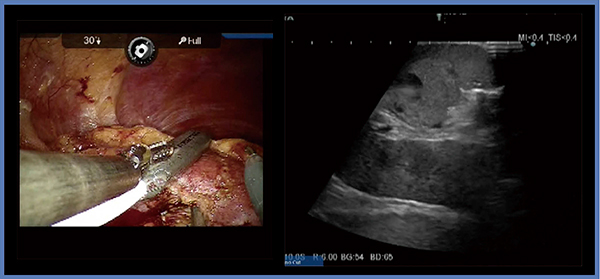

症例3は,45歳,男性,2.3cmの右腎細胞がんである(図4)。腫瘍は完全に埋没しているが,症例2と同様のアプローチで切除を進めていく。本症例は背側に腫瘍があったため,腎の受動性を十分確保し,腎動静脈や腎盂をその走行が確認できるよう剥離しておくことで,安全な切除が可能となる。症例2と同様に腎盂,腎動静脈から腫瘍底をある程度剥離した後にエコーで腫瘍の位置を確認すると,腫瘍被膜まで十分剥離できていることが確認できる(図4右)。このような,LPNでは腎実質の欠損がかなり大きくなると思われる症例も,RAPNにて最小限のマージンで切除可能である。本症例も,縫合は腎実質一層のみとしている。阻血時間は17分と比較的短時間であり,腎機能(s-Cre)の低下も,術前が0.59mg/dL,術後が0.65mg/dLと最小限にとどめることができた。

図4 症例3:右腎細胞がん(45歳,男性)